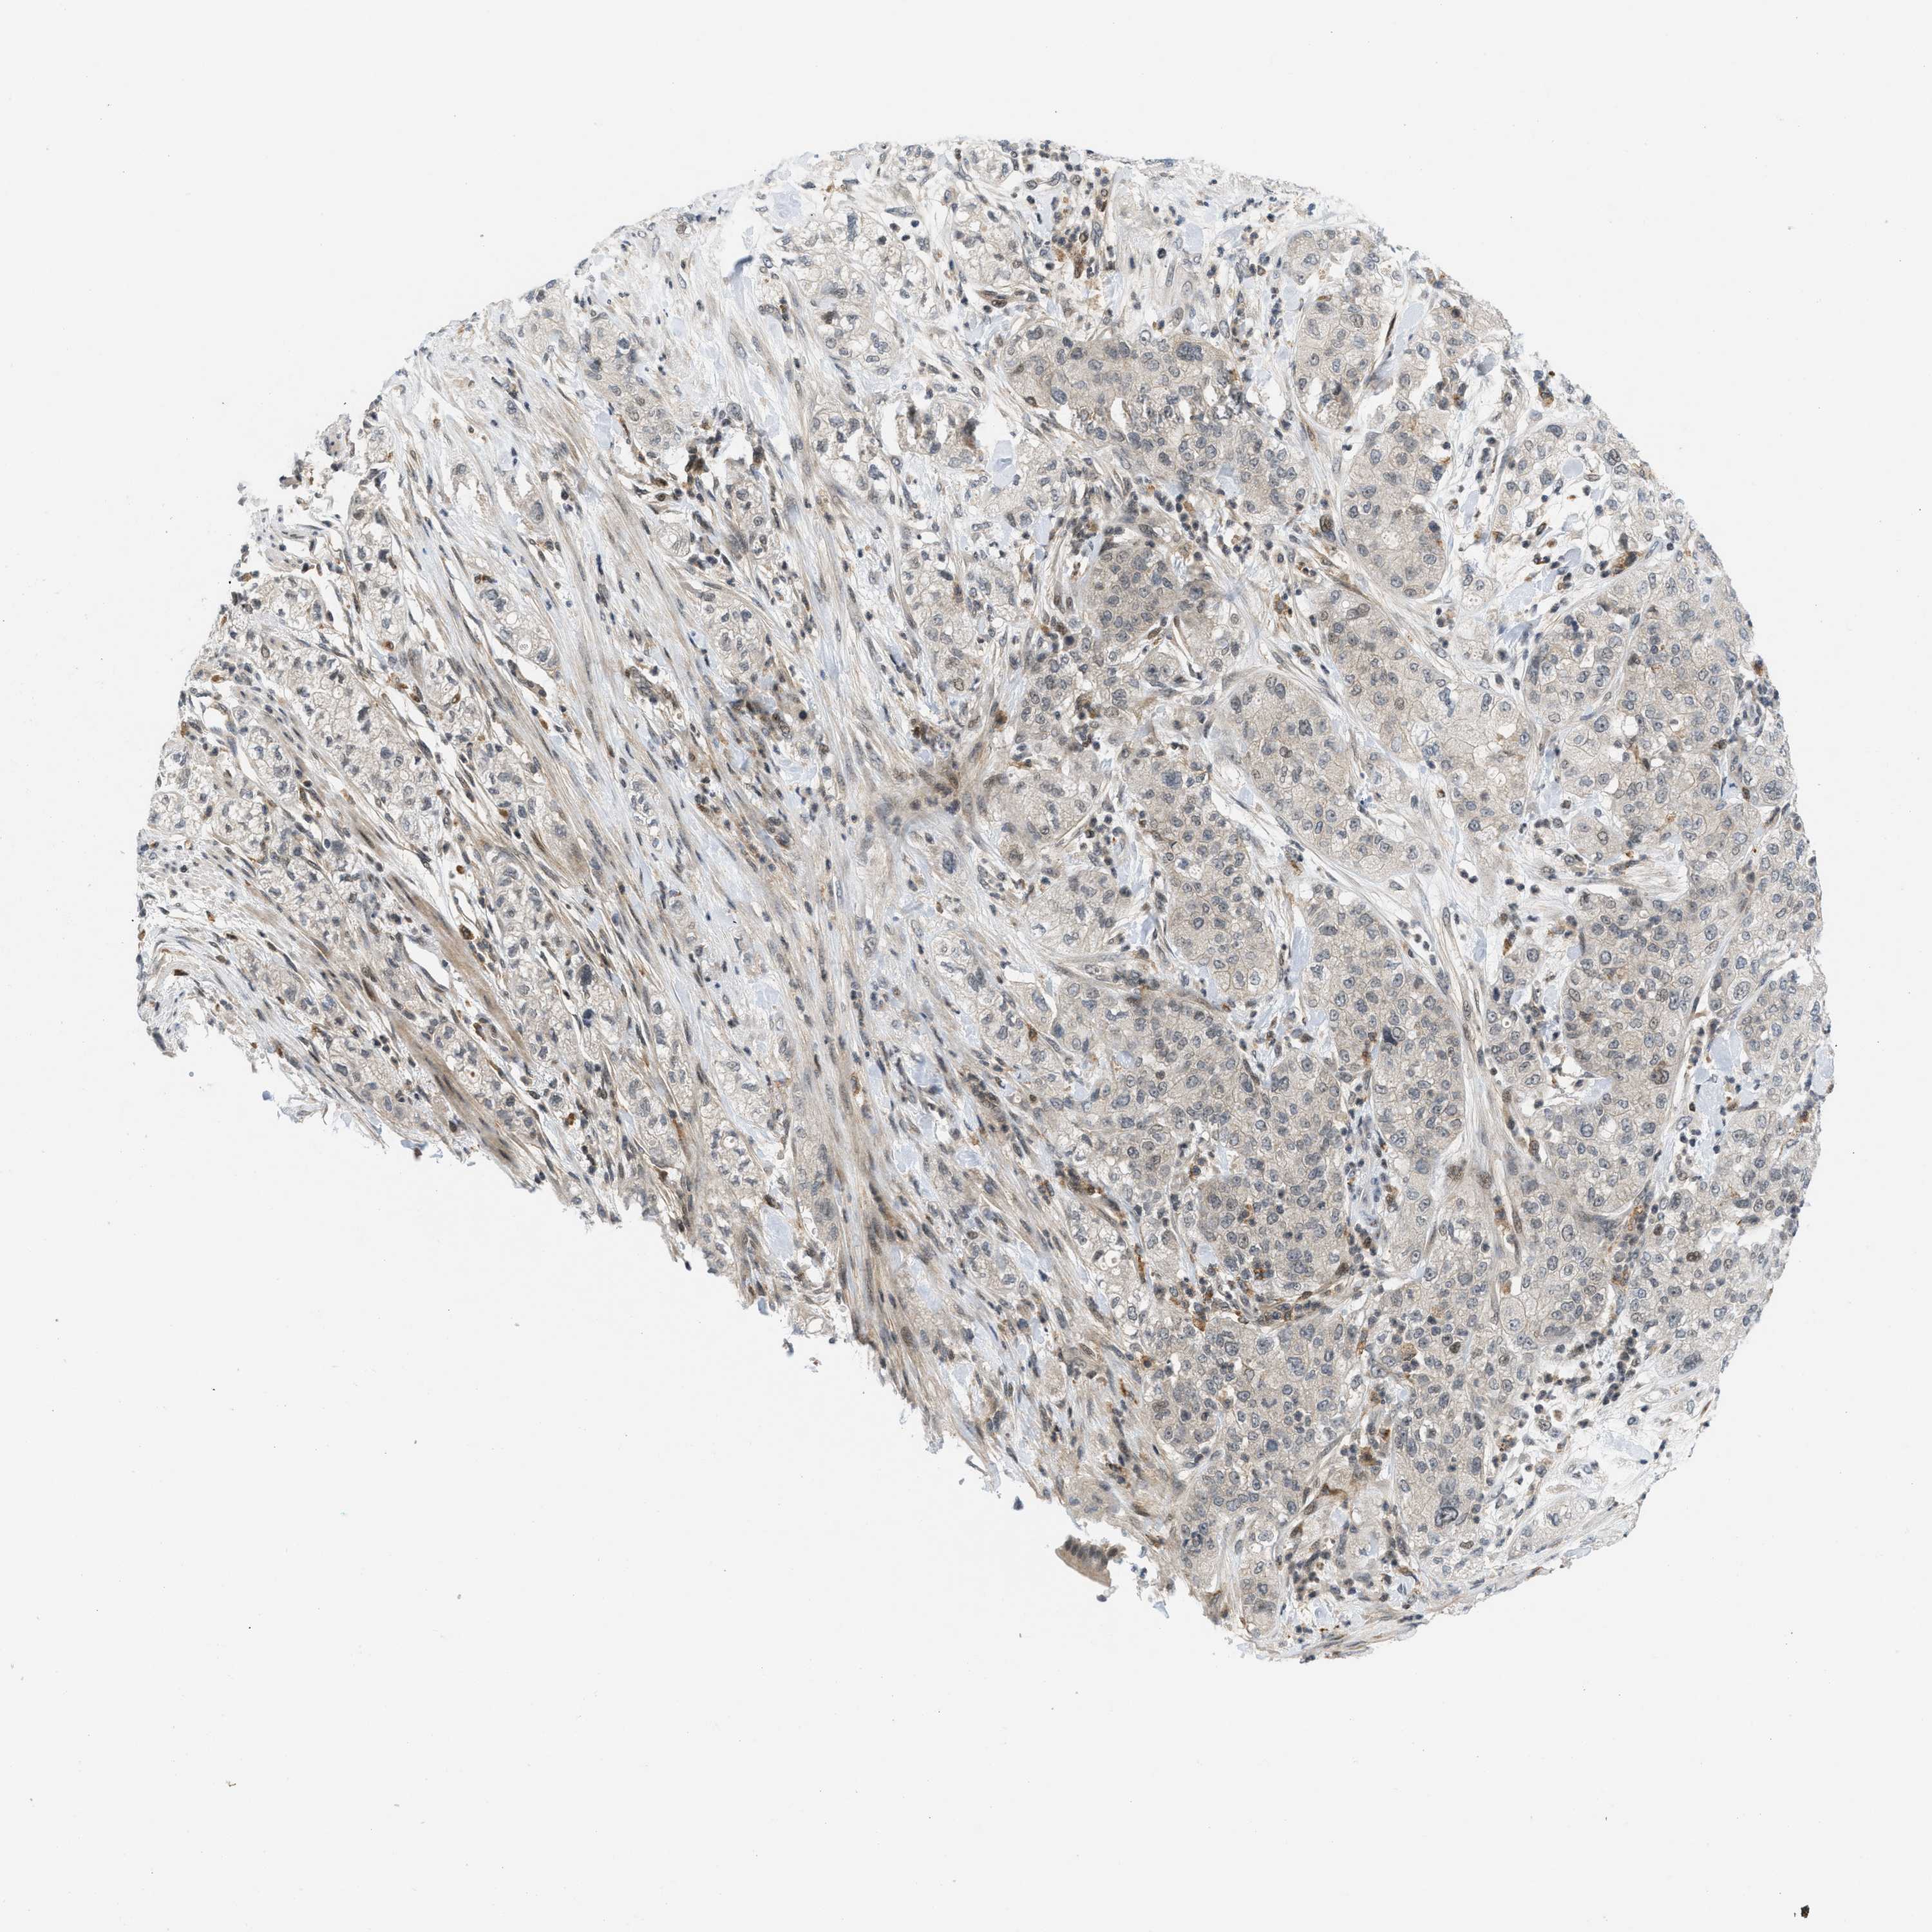

PANCREATIC CANCER - Protein expressioni

A mouse-over function shows sample information and annotation data. Click on an image to view it in a full screen mode. Samples can be filtered based on level of antibody staining by selecting one or several of the following categories: high, medium, low and not detected. The assay and annotation is described here.

Note that samples used for immunohistochemistry by the Human Protein Atlas do not correspond to samples in the TCGA dataset.

Antibody stainingi

Antibody staining in the annotated cell types in the current human tissue is reported as not detected, low, medium, or high, based on conventional immunohistochemistry profiling in selected tissues. This score is based on the combination of the staining intensity and fraction of stained cells.

Each image is clickable and will lead to virtual microscopy that enables deeper exploration of all samples and also displays staining intensity scores, fraction scores and subcellular localization as well as patient and tissue information for each sample.

Antibody CAB016136

Antibody CAB017773

Staining

High

Medium

Low

Not detected

Intensity

Strong

Moderate

Weak

Negative

Quantity

>75%

75%-25%

<25%

None

Location

Nuclear

Cytoplasmic/membranous

Cytoplasmic/membranous,nuclear

Adenocarcinoma, NOS

Adenocarcinoma, metastatic, NOS